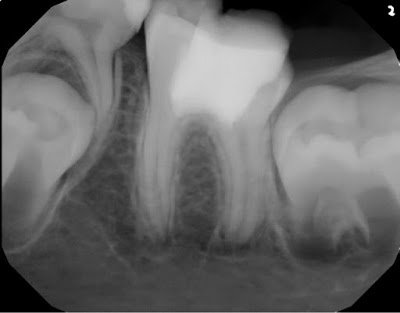

2 year recall reveals a symptomatic tooth with full function. Roots have continued to develop to normal length and thickness. Coronal protection recommended.